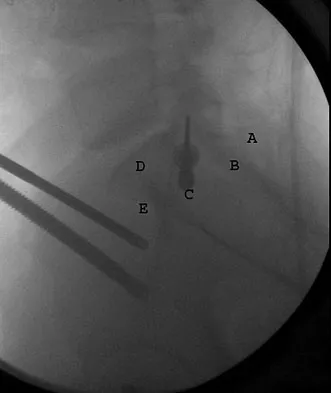

Question 97High Yield

What letter in Figure 33 marks the correct starting point for a transiliac pelvic screw?

Explanation